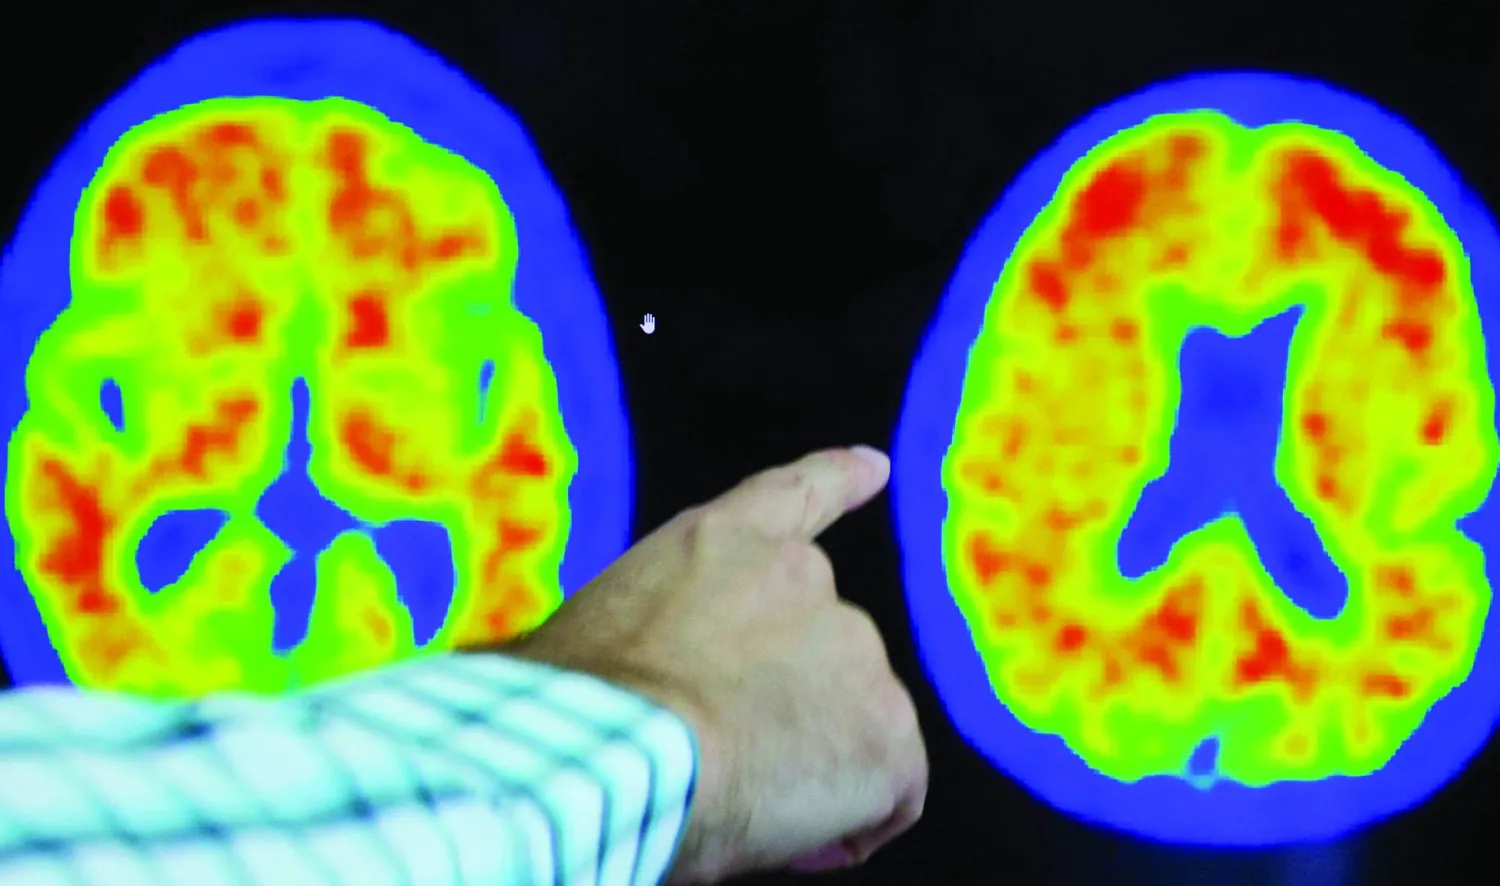

وألزهايمر هو مرض عصبي تنكسي يتميز بالتدهور التدريجي للوظائف المعرفية، مثل الذاكرة، واللغة، والتفكير، والسلوك، والقدرات على حل المشكلات. وهو السبب الأكثر شيوعاً للخرف؛ حيث يمثل 60-80 في المائة من الحالات.